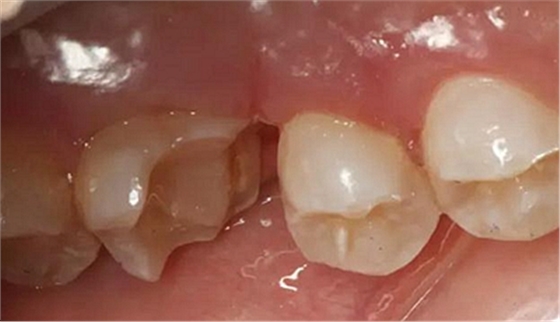

病例一 女性,20歲,大學(xué)生,要求補(bǔ)牙,檢查口內(nèi)可見A6大面積缺損,近中牙齦息肉,拍X片,根管充填物略差,但根周未見明顯陰影,口內(nèi)檢查無叩痛。建議患者冠延長手術(shù)+高嵌體修復(fù)。

患牙遠(yuǎn)中邊緣嵴完整,強(qiáng)度沒有降低,故擬保留遠(yuǎn)中邊緣嵴,高嵌體修復(fù)。首先去除腐質(zhì)及原墊底材料,流體樹脂+3M Z350XT樹脂墊底。局麻下行冠延長手術(shù)。在此需要提及個人的一個觀點(diǎn)。冠延長手術(shù)原則上要求3-6個月以上才能永久修復(fù)。但是個人喜歡后牙肩臺建立在齦上,所以修復(fù)后的修復(fù)體邊緣位于牙齦上方1mm,對牙周的愈合影響較小(如果為齦下邊緣則要慎重),故該患者術(shù)中按照齦上邊緣的設(shè)計(jì)進(jìn)行冠延長手術(shù)。以下為術(shù)中: